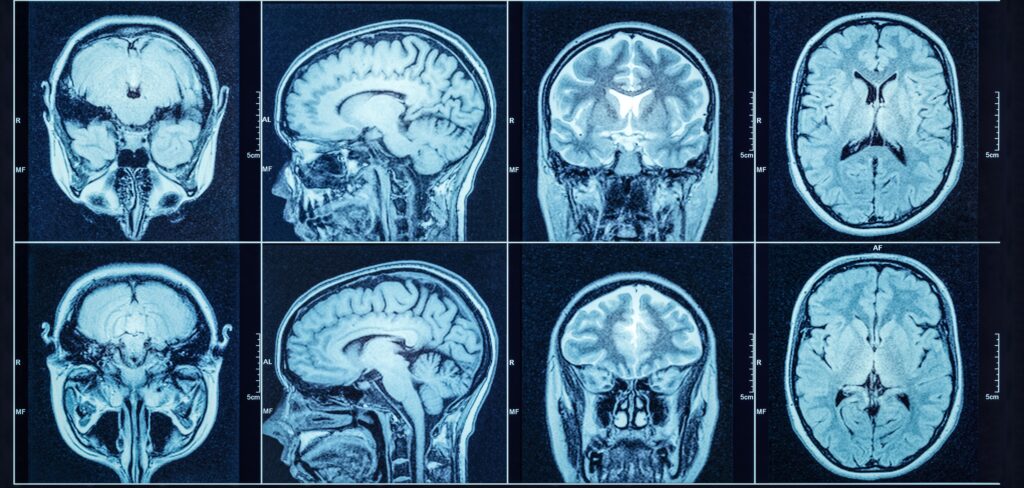

Brain Cancer Symptoms, Causes & Types – What Patients Should Know

Being diagnosed with brain cancer can feel overwhelming, but treatment has come a long way. Depending on the type, size, location, and whether the tumor is benign or malignant, your care team will develop a personalized plan to provide the best chance for recovery and quality of life.

Brain Cancer Awareness—Know the Signs, Share the Facts

Brain Cancer Awareness is about more than a diagnosis—it’s about education, early detection, and support for those impacted. Although brain cancer is relatively rare, it can be life-altering. Raising awareness helps ensure symptoms aren’t ignored and encourages people to seek timely care.